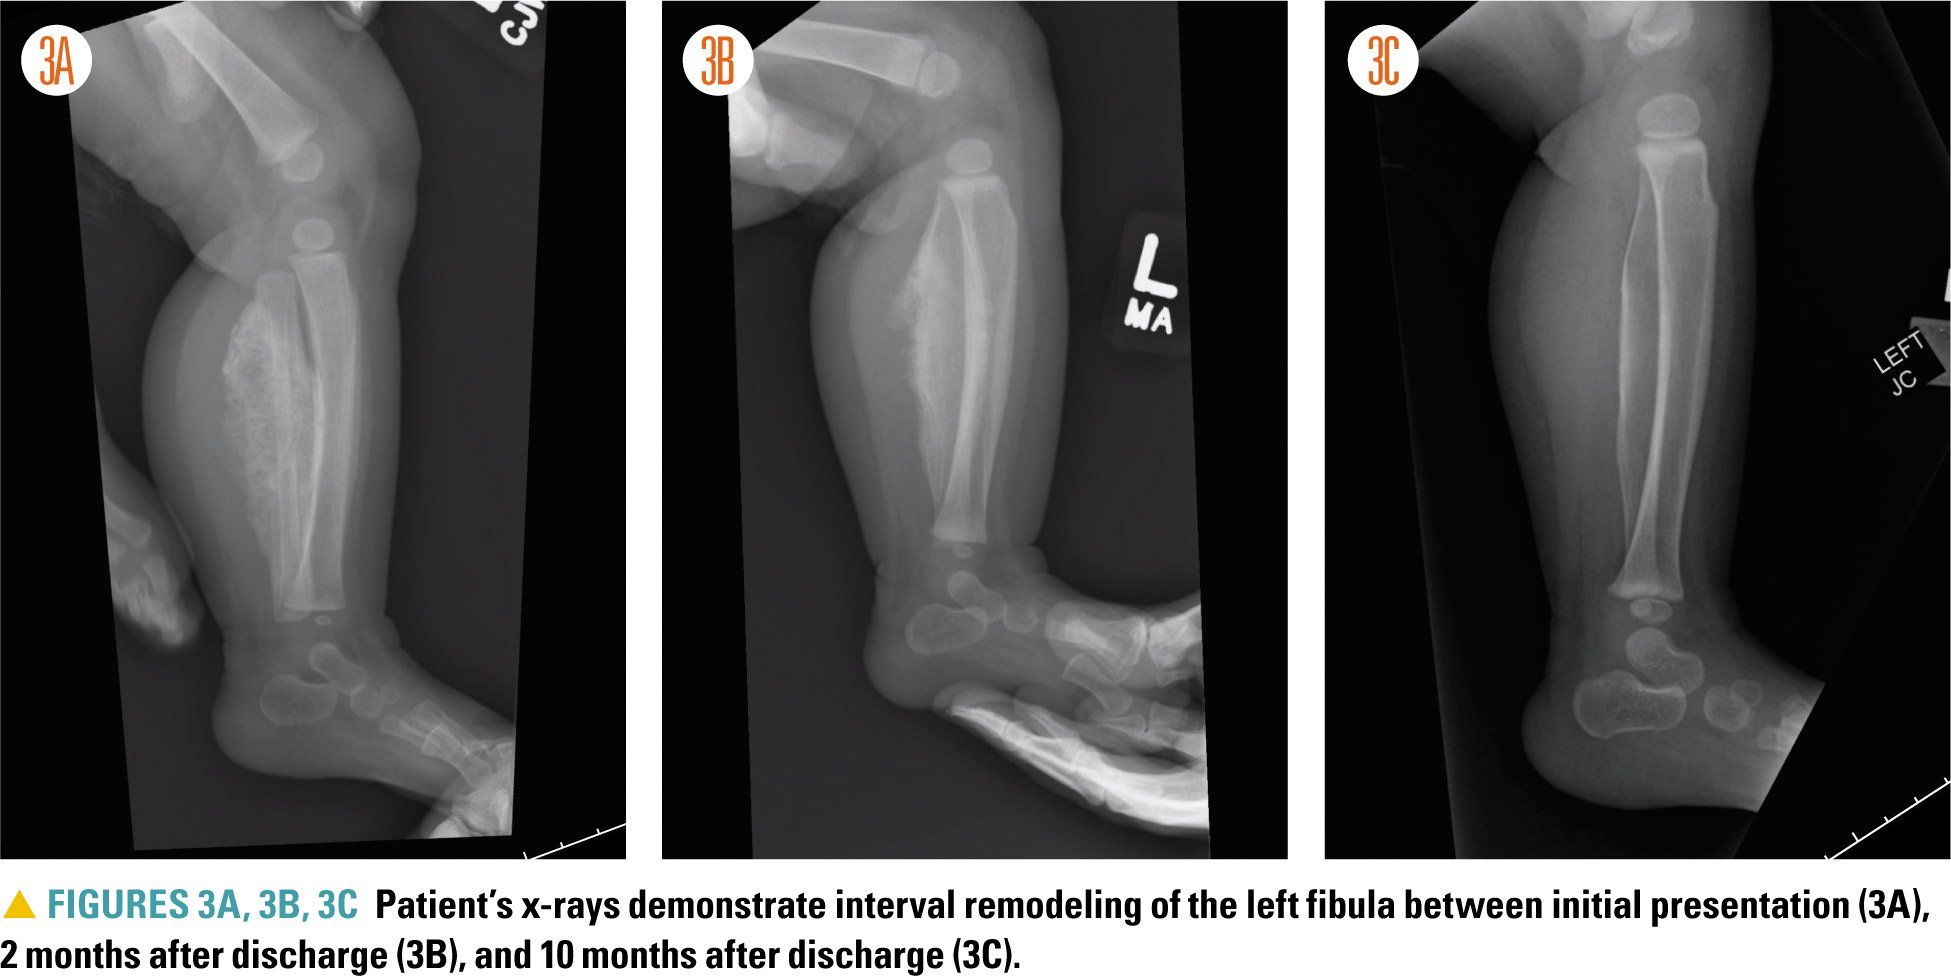

Figures 3A, 3B, and 3C

For this patient, no additional imaging was obtained, and she did not require any medical or surgical intervention. She was discharged home with plans to follow up with Orthopedic Surgery. Serial x-rays obtained during outpatient clinic visits with Orthopedic Surgery demonstrated interval bone remodeling (Figures 3A, 3B, 3C), with marked improvement and minimal residual deformity noted 10 months after discharge.